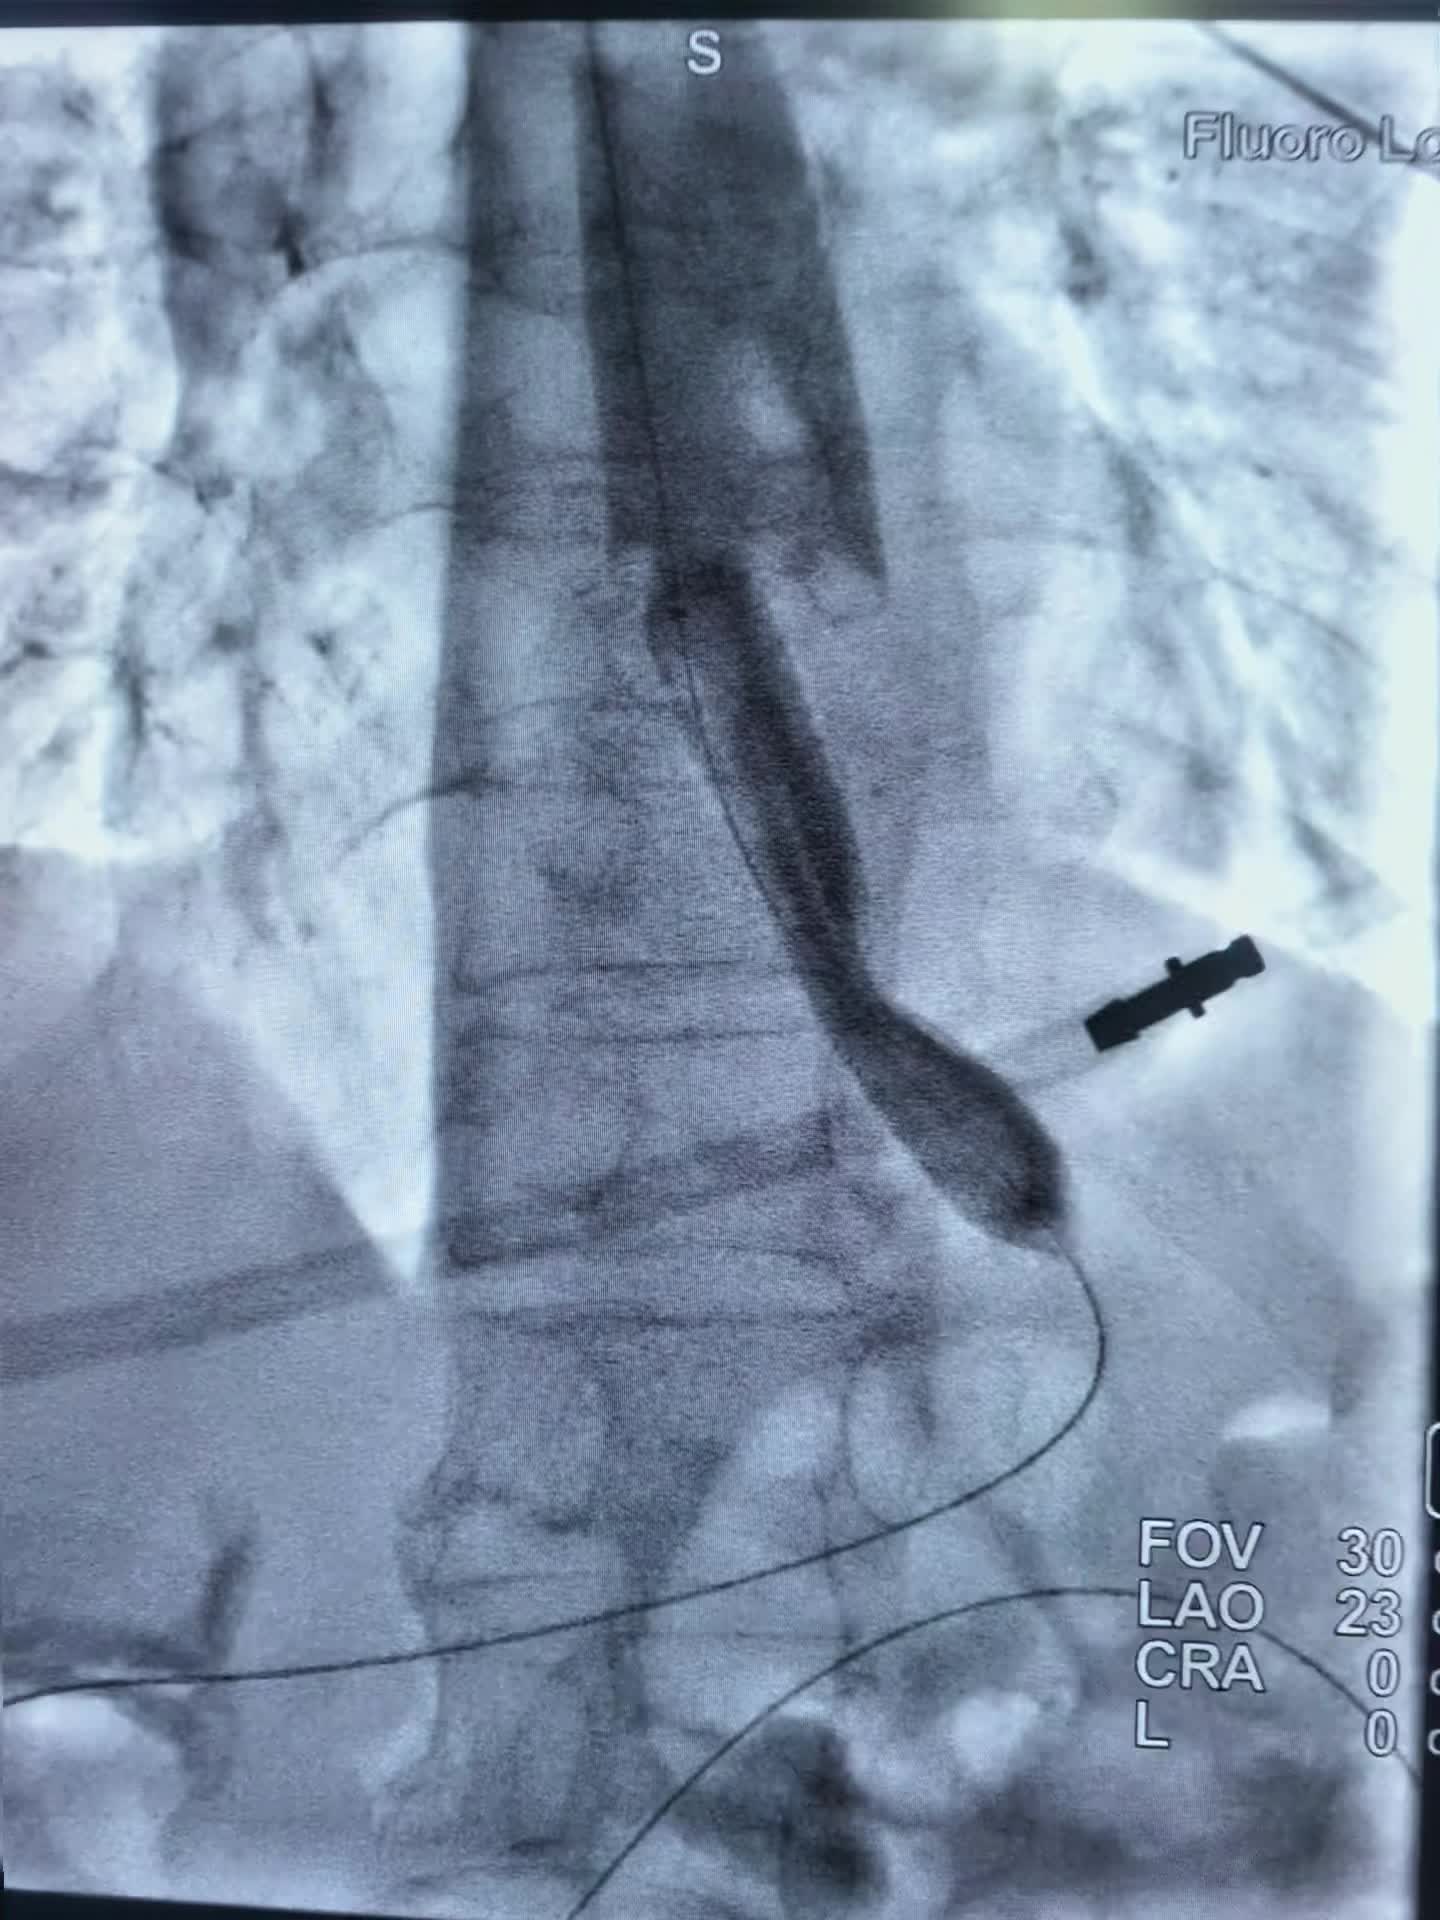

上午第一台78岁老年男性贲门癌患者,突发食管梗阻不能进食水,行球囊扩张,食管支架置入术,术即可恢复饮食。 第二台:食管癌术后3年再次进食哽咽,食管吻合口狭窄伴肠管膈肌处狭窄。单纯行球囊扩张术,术后即可恢复正常饮食。